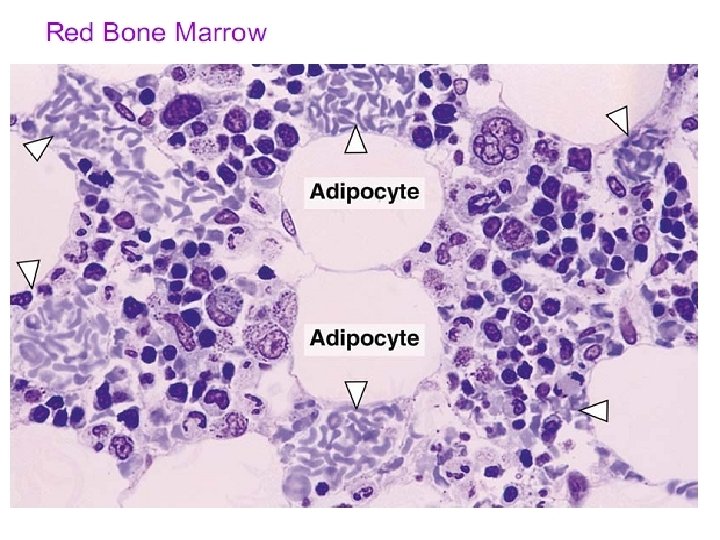

BONE MARROW The marrow of all bones begins as active hematopoietic tissue or red marrow(RBM). During growth, development, and aging, portions of the active red marrow are replaced by adipocytes to form yellow marrow(YBM). 1. Stroma consists of adipocytes (up to 75% of red marrow), macrophages, and reticular connective tissue composed of reticular cells, adventitial cells and the reticular fibers (type III collagen). Adventitial cells are highly branched, poorly differentiated mesenchymal derivatives resembling fibroblasts. Their processes separate the developing blood cells from the endothelium of the bone marrow sinusoids.

2. Hematopoietic cords fill the interstices of the stroma and are crowded with overlapping blood cells of all types and at all stages of differentiation. RBM is composed of interdigitating masses of stroma and hematopoietic cords. 3. Abundant sinusoids lie between the cords and have openings in their walls through which maturing blood cells and platelets enter the circulation. In histologic section, the dense packing of the cells makes identification of individual cell types difficult. Thus, differentiating blood cells are commonly studied in smears. 4. Erythroblastic islands are clusters of developing erythrocytes surrounding macrophages and receiving iron from them.

Bone Marrow • Bone marrow is a general term for the soft tissue occupying the medullary cavity of a long bone, the spaces amid the trabeculae of spongy bone, and the larger haversian canals. • There are 2 main types: red & yellow. • Red bone marrow = blood cell forming tissue = hematopoietic tissue • Red bone marrow looks like blood but with a thicker consistency. • It consists of a delicate mesh of reticular tissue saturated with immature red blood cells and scattered adipocytes. Notice the red marrow and the compact bone